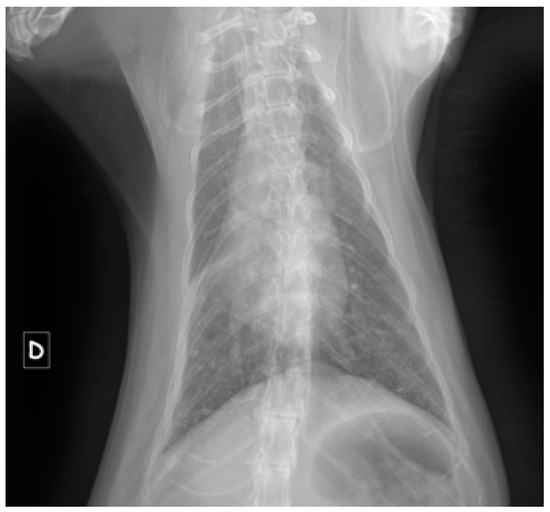

3.4. Results for Cats in Group T—Traumatic Origin